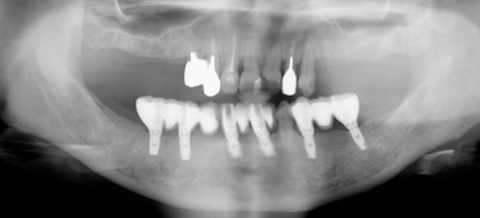

治療後

下顎に6本のインプラントにより固定式ブリッジになりました。ご自身の歯と同様に食事ができます。患者様も何十年ぶりに、きちんと食事もでき、審美的にも満足できると 非常に喜んでいただけました。現在上顎は義歯ですが、インプラントも考えているそうです。

患者はインプラント治療を希望していても、歯を抜歯し義歯(入れ歯)を作成することから始めます。理由は咬みあわせを回復し、咬合を確認することと、義歯で対応できればそれでよいのですから。上顎の義歯は違和感があるものの使用はできましたが、下顎の義歯は違和感が強くまったく使用でいない状態でした。そこで、下顎にはインプラントを埋入し、完全固定式のブリッジを作成する計画を立てました。

下顎の骨の状態は良好なので、即時荷重(インプラント埋入と同時に仮歯がはいり咬めるようになる治療)を行いました。